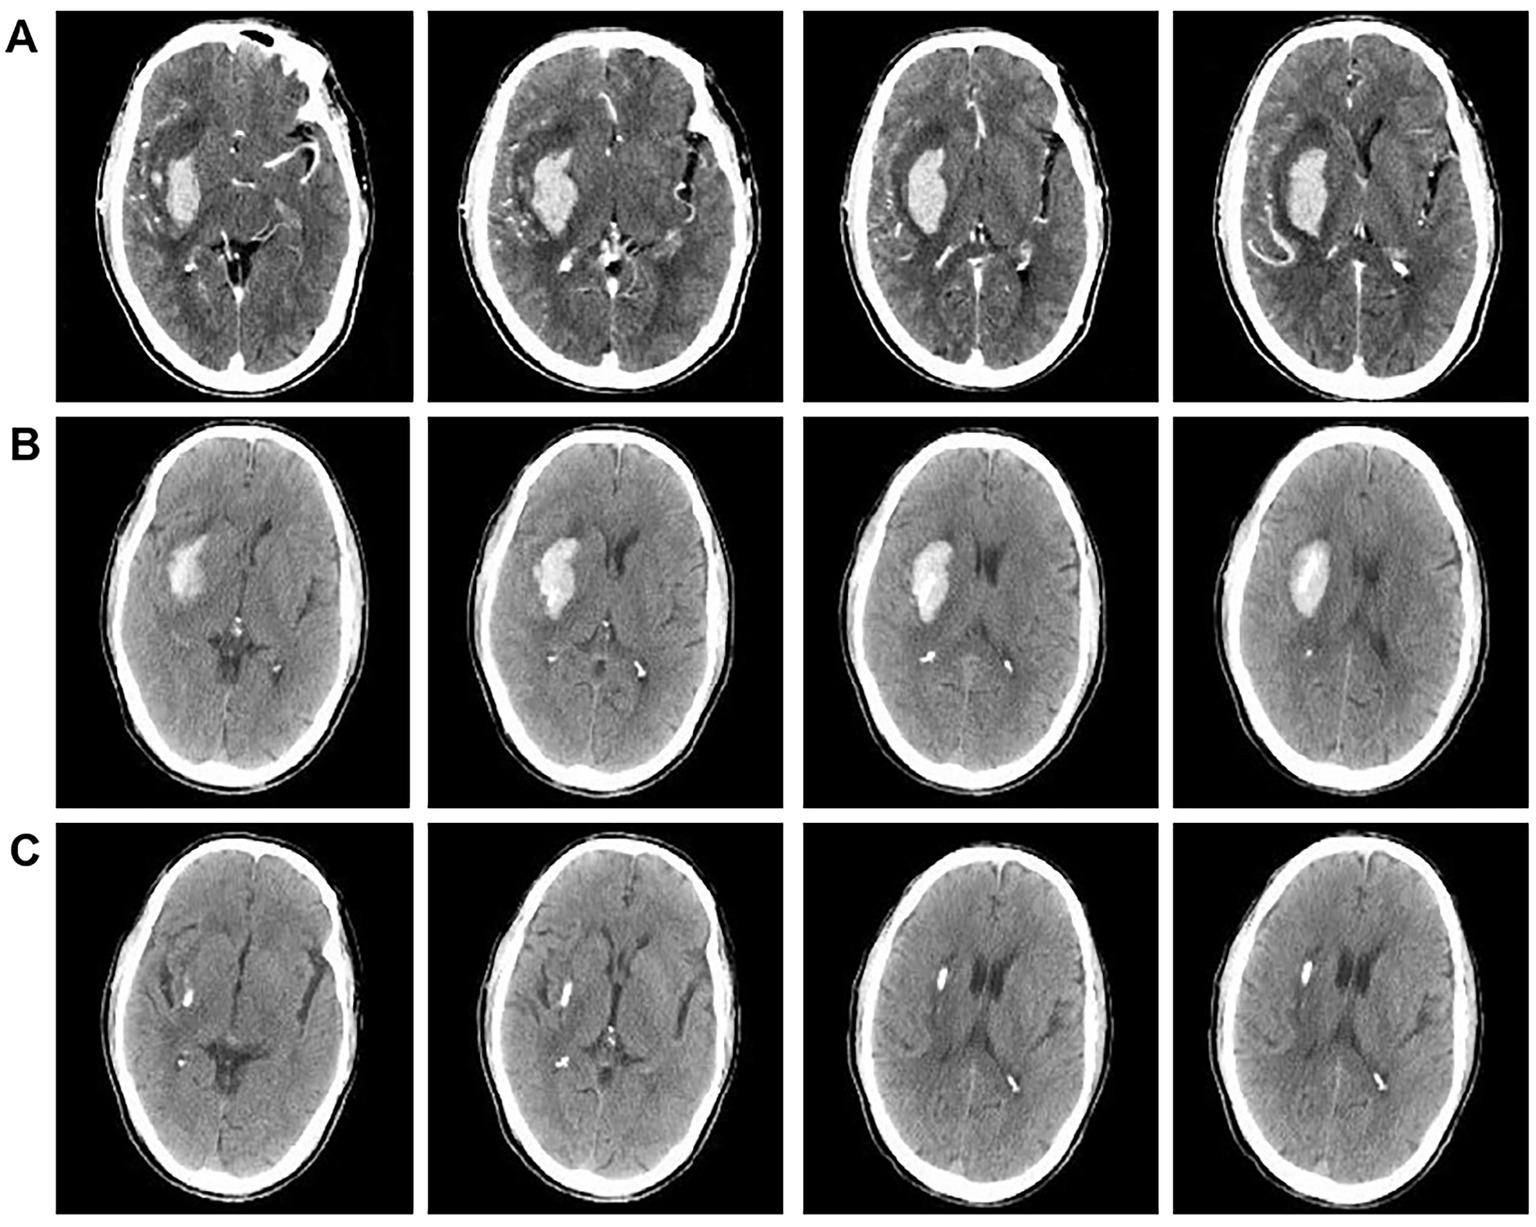

Figure 4

CT Comparison images before and after medication intervention treatment. (A) Brain CTA scan images of patients upon admission. (B) Brain CT scans of patients after 3 days post-admission. (C) Brain CT scans of patients after 7 days post-admission.

2.6 Medicinal conservative therapy

Medication intervention encompasses tranquil relaxation, airway clearance, monitoring of body temperature, blood pressure, and respiration rate, as well as managing cerebral edema, among other aspects. Typically, regardless of whether antihypertensive medications are administered intravenously or orally, the average reduction in arterial pressure during the initial phase (≤1 h) remains within 25.0% of the baseline level, achieving a safe threshold (approximately 160/100 mmHg) within 2–6 h, and returning to normal levels within 24–48 h. If a critical organ experiences ischemia during the process of lowering blood pressure, the duration may extend to 1–2 weeks. Furthermore, the active management of brain edema and a decrease in intracranial pressure are critical components of the therapy for acute cerebral hematoma. This trial administered 3–5 mL/kg of mannitol intravenously within 15–30 min to patients exhibiting signs of intracranial hypertension, including headache, vomiting, and papilledema, effectively managing brain edema and lowering intracranial pressure, resulting in favorable clinical efficacy. Furthermore, dietary support, neuronal health, maintenance of fluid and electrolyte equilibrium, and proactive avoidance and management of associated problems are critical elements of the therapeutic approach. Figure 4 shows the therapeutic efficacy of medication intervention.